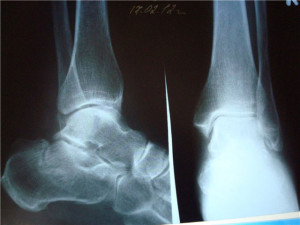

При обращении в травмпункт пациенту обязательно будет назначено рентгеноскопическое обследование.

Диагностика

Имея часть клинической картины (характерную симптоматику), врач проводит осмотр и направляет на рентгенографию стоп обеих конечностей. Рентген делается в двух проекциях: боковой и аксиальной. Снимок требуется для того, чтобы:

Поэтому и нужен рентген обеих стоп (больной и здоровой). Первое, на что обращает внимание специалист при чтении снимка, – каков суставно-бугорный угол (угол Белера). Нормальное значение этого угла – 20-40 градусов. При травме пятки значение угла изменяется – уменьшается или даже уходит в минус. Исходя из этого критерия, пациента будут лечить соответственно.

Рентгенография – наиболее быстрый и общедоступный метод исследования для постановки правильного диагноза. Иногда пациенту назначается КТ, что позволяет получить более четкую картинку места повреждения костных тканей и прилегающих мягких. Однако компьютерная томография применима не всегда.